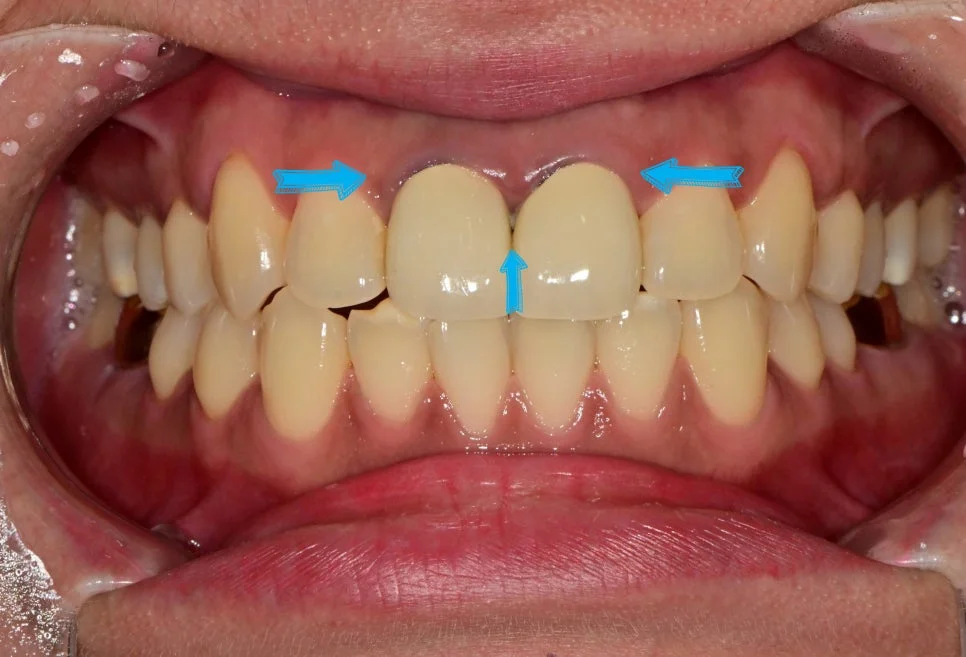

이번 포스팅에서 소개할 내용은 앞니를 신경치료 후 크라운을 씌웠는데, 점점 잇몸이 검게 변한 경우인데요.

이 환자분은 “웃을 때마다 검게 변한 잇몸과 앞니가 싫다”라며 내원하셨고, 소문난 미백 맛집 치과답게 아름답게 심미적인 부분을 회복시켜드린 사례이니 실제 예시를 통해 보실까요!

앞니 크라운 잇몸 변색으로 검게 그을린 듯한 잇몸이 관찰되었는데요.